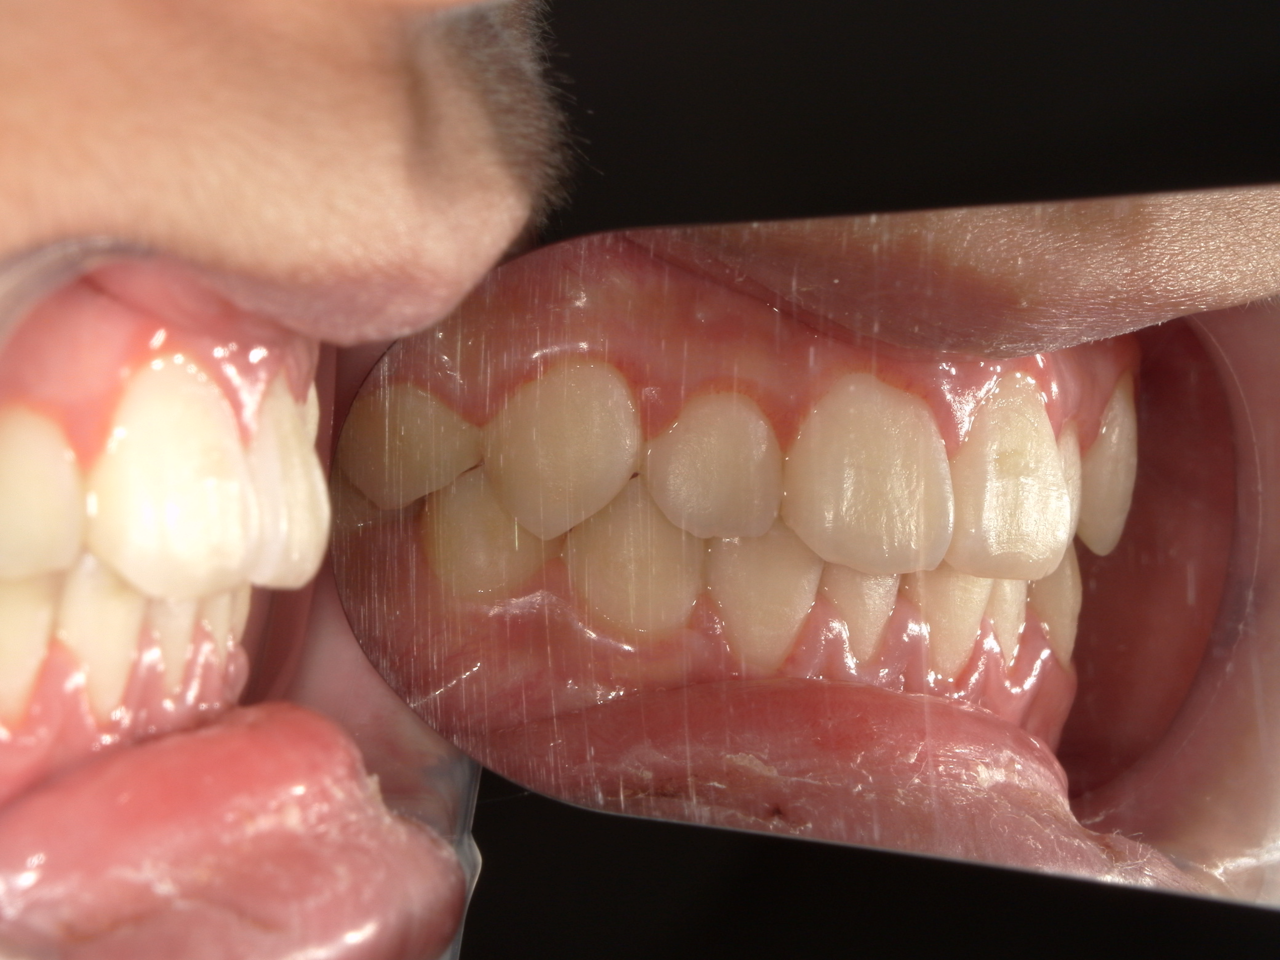

治療前

治療説明

歯科矯正で取り外し可能な矯正方法である床矯正とチンキャップで治療しました

治療期間 4年6か月

治療費用300000 円

治療後

治療の副作用(リスク)歯の動き方には個人差があり、予想された治療期間が延長する可能性があります。。床矯正の使用状況、矯正歯科治療には患者さんの協力が必要であり、それらが治療結果や治療期間に影響します。2次矯正が必要になる場合もあります。